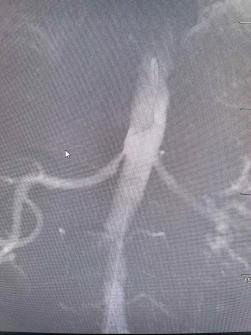

鉴于王阿姨年龄较大,经过多学科会诊后,市三医介入血管外科主任张煜杰为其进行了微创介入手术,从左侧肱动脉穿刺置入鞘管,用微导丝通过狭窄血管后,用球囊扩张支架撑开狭窄的血管,改善肾脏的供血,从根本上遏制了刺激血压升高的因素。患者术后血压逐渐回落。目前,患者情况稳定,口服一种药物就能很好地控制血压了。

张煜杰主任介绍,肾动脉高血压的发生是由于肾动脉狭窄导致肾脏缺血,激活了人体肾素血管紧张素-醛固酮系统而引起的继发性血压升高,单纯口服降压药物控制不佳。一旦控制不好,就会发生脑梗、脑出血等情况,危及生命健康,通过血管介入治疗的方式,植入支架,解除了肾动脉狭窄,改善了肾脏供血,进而从根本上控制了血压。

肾动脉狭窄是继发性高血压最常见的原因之一,主要由动脉粥样硬化引起。对于疑似患者,首选非侵入性的超声进行诊断。无症状、偶然发现的肾动脉狭窄不需要血运重建。对于需要血运重建的有症状患者,肾动脉支架植入术是首选疗法。所有肾动脉狭窄患者均应接受指南指导的药物治疗,包括高血压控制、糖尿病控制、他汀类药物、抗血小板治疗、戒烟等。